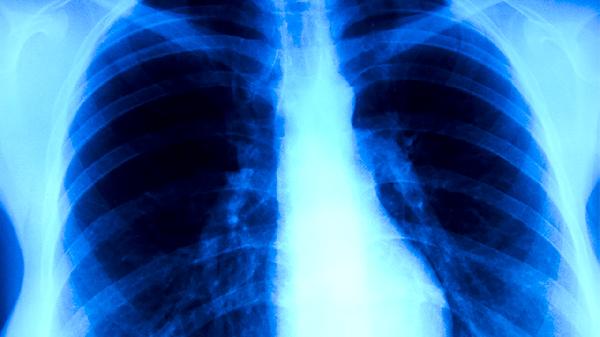

百合粥含有百合、粳米等食材,百合具有潤肺止咳功效,對肺結(jié)核引起的干咳、痰中帶血等癥狀有一定緩解作用。粳米能補(bǔ)中益氣,為患者提供基礎(chǔ)能量支持。但百合粥中的有效成分濃度遠(yuǎn)不足以殺滅結(jié)核分枝桿菌,無法替代異煙肼片、利福平膠囊等抗結(jié)核藥物。肺結(jié)核患者可能出現(xiàn)午后低熱、夜間盜汗、體重下降等典型癥狀,需通過痰涂片檢查、胸部CT等明確診斷。

肺結(jié)核屬于乙類傳染病,病原體為結(jié)核分枝桿菌,必須遵循早期、聯(lián)合、規(guī)律、全程用藥原則。標(biāo)準(zhǔn)治療方案通常包含異煙肼片、利福平膠囊、吡嗪酰胺片、乙胺丁醇片等藥物聯(lián)用,療程需持續(xù)6-9個月。不規(guī)范治療可能導(dǎo)致耐藥結(jié)核病,增加治療難度?;颊邞?yīng)嚴(yán)格遵醫(yī)囑用藥,定期復(fù)查肝功能、胸部影像學(xué)等指標(biāo)。